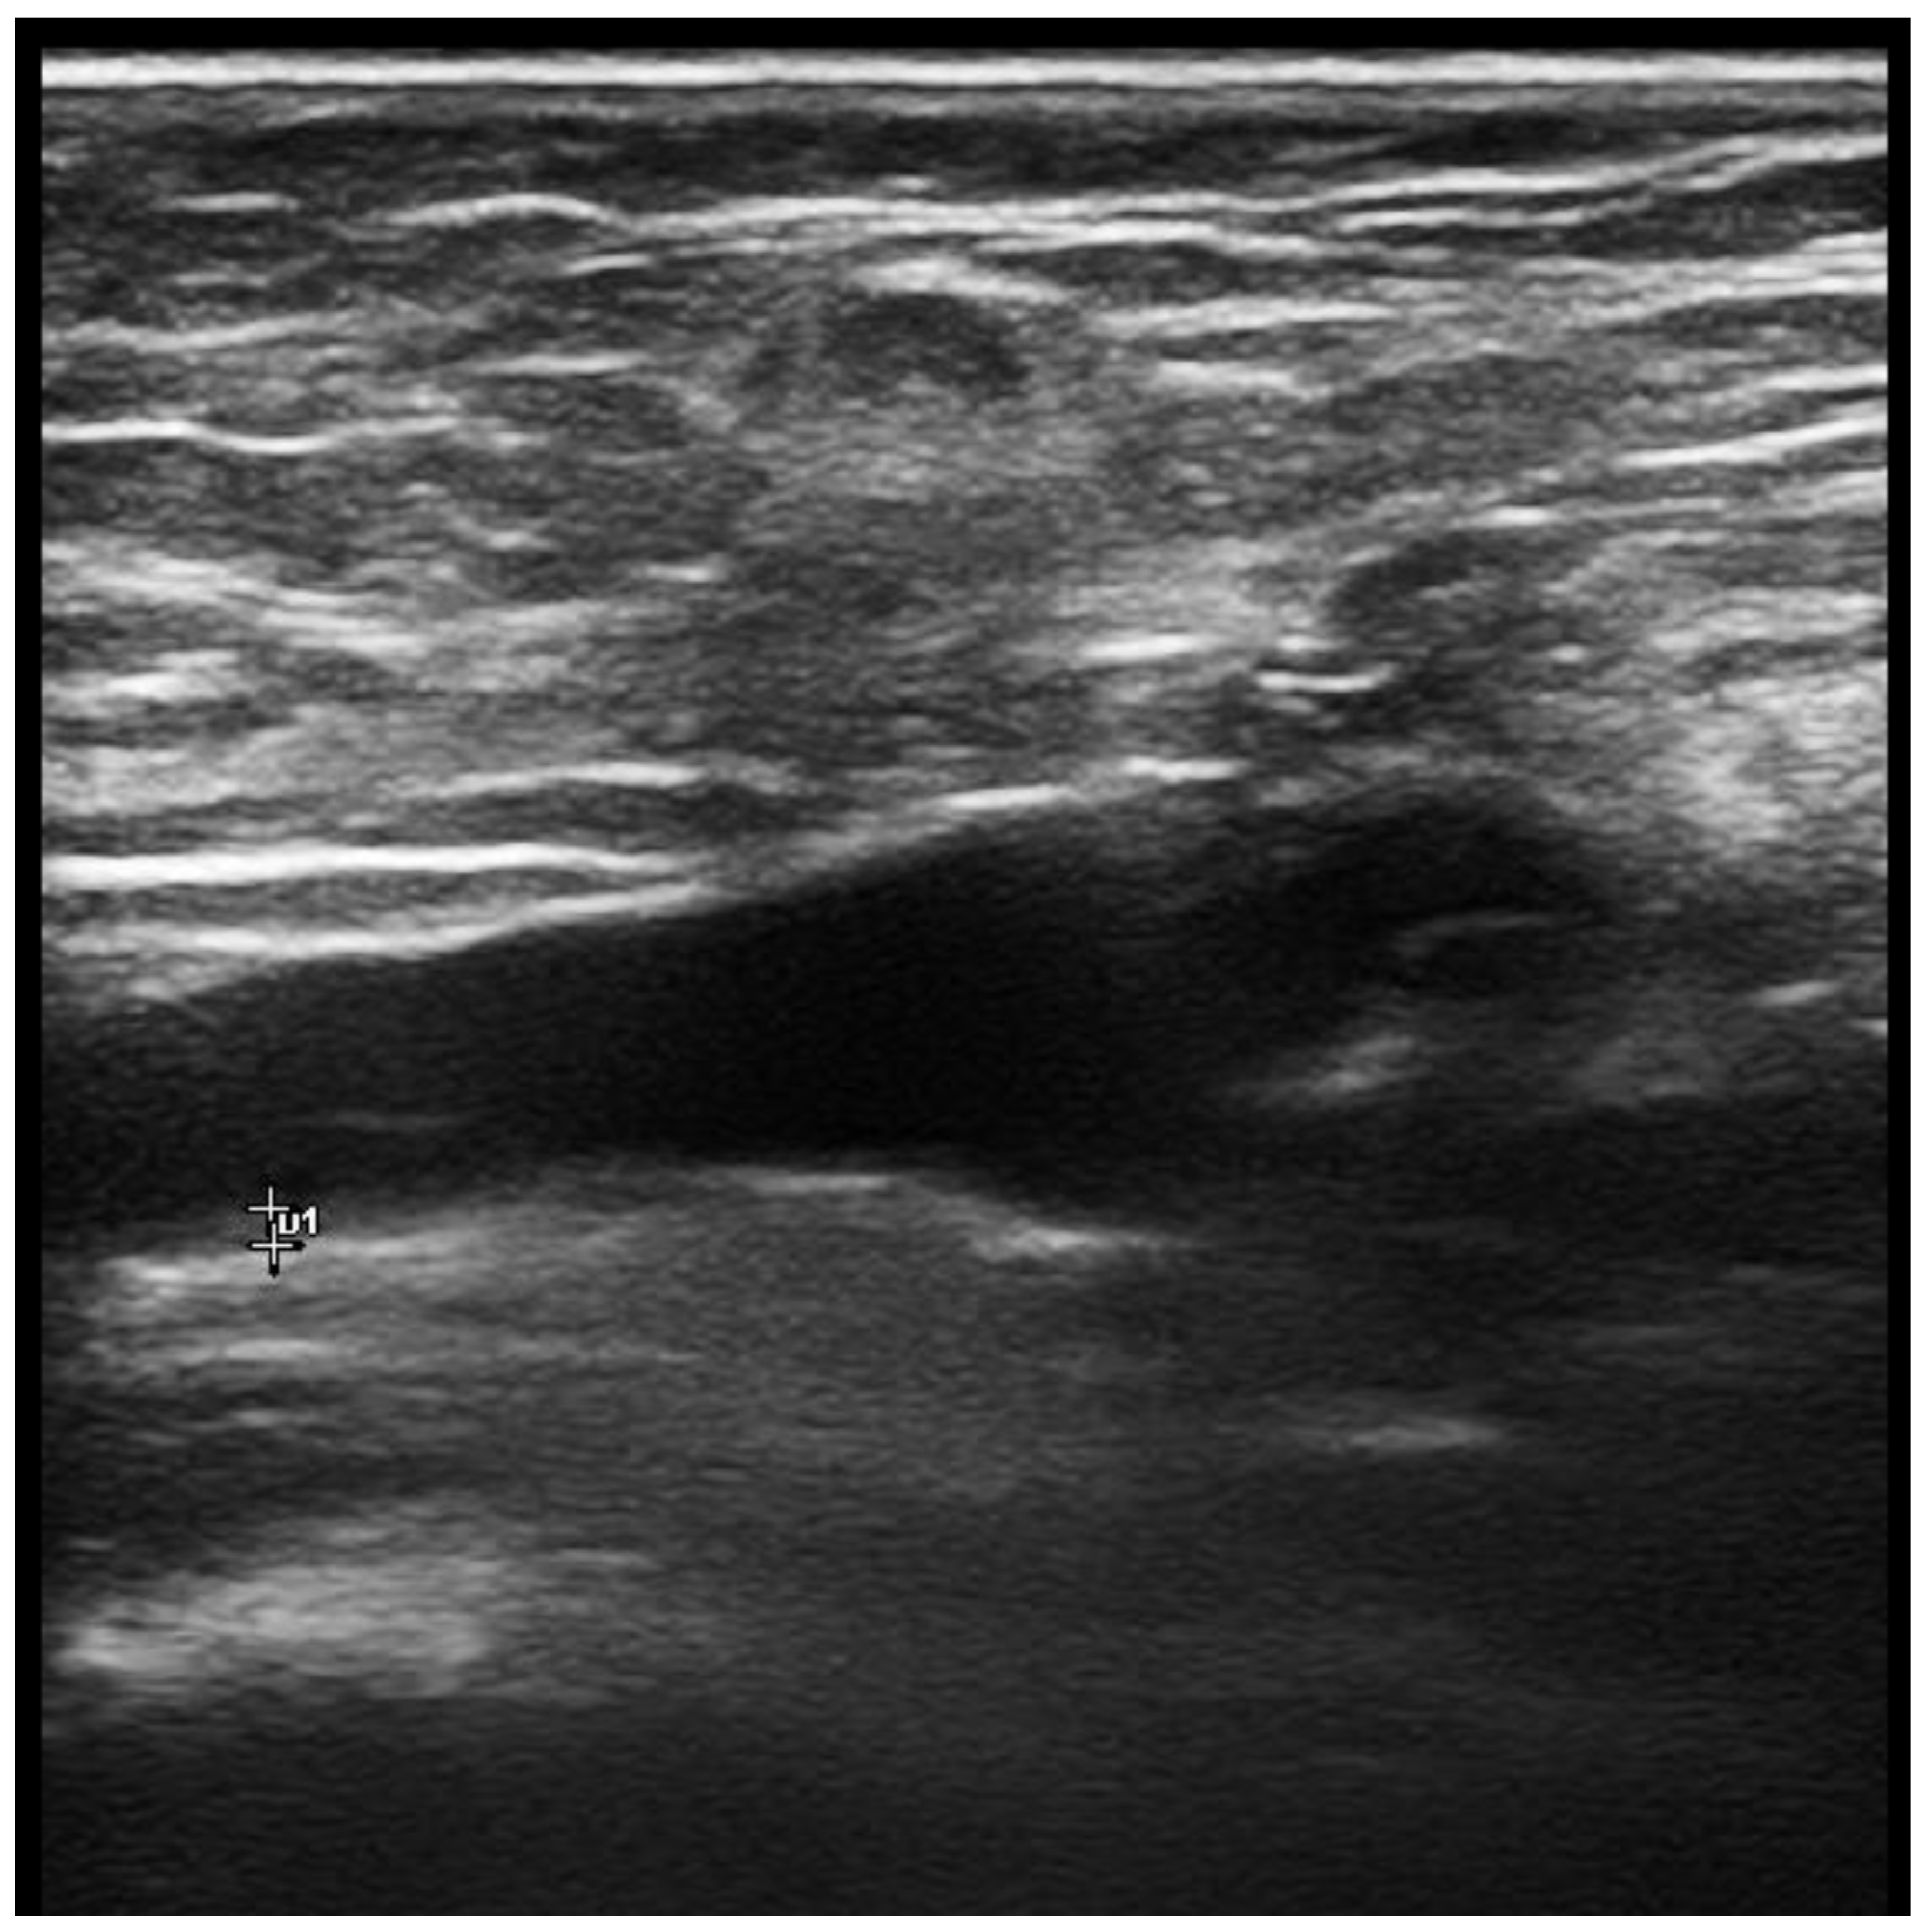

6. Femoral Vein Wall Thickness Measurement as a Diagnostic Tool for Behcet’s Disease

- Alibaz-Oner, F.; Direskeneli, H. Assessment of venous wall thickness with Doppler ultrasonography may be a diagnostic tool for Behçet’s disease. Int. J. Rheum. Dis. 2019, 22, 767–768. [Google Scholar] [CrossRef]

- Boulon, C.; Skopinski, S.; Constans, J. Vein inflammation and ultrasound in Behçet’s syndrome. Rheumatology 2016, 55, 1750. [Google Scholar] [CrossRef]

- Alibaz-Oner, F.M.A.; Ergelen, R.; Erturk, Z.; Ergun, E.; Direskeneli, D. Venous vessel wall thickness in lower extremity is increased in male behcet’s disease patients without vascular involvement. Rheumatology 2017, 56, 56. [Google Scholar]

- Alibaz-Oner, F.; Ergelen, R.; Mutis, A.; Erturk, Z.; Asadov, R.; Mumcu, G.; Ergun, T.; Direskeneli, H. Venous vessel wall thickness in lower extremity is increased in male patients with Behcet’s disease. Clin. Rheumatol. 2019, 38, 1447–1451. [Google Scholar] [CrossRef]

- Seyahi, E.; Gjoni, M.; Durmaz, E.; Akbaş, S.; Sut, N.; Dikici, A.S.; Mihmanli, I.; Yazici, H. Increased vein wall thickness in Behçet disease. J. Vasc. Surg. Venous. Lymphat. Disord. 2019, 7, 677–684.e672. [Google Scholar] [CrossRef]

- Tezcan, D.; Özer, H.; Gülcemal, S.; Hakbilen, S.; Durmaz, M.S.; Batur, A.; Yilmaz, S. Diagnostic Performance of Lower Extremity Venous Wall Thickness and Laboratory Findings in the Diagnosis of the Behçet Disease. J. Clin. Rheumatol. 2022, 28, e521–e527. [Google Scholar] [CrossRef]

- Kaymaz, S.; Yilmaz, H.; Ufuk, F.; Ütebey, A.R.; Çobankara, V.; Karasu, U.; Albayrak Yaşar, C.; Ulutaş, F. Ultrasonographic measurement of the vascular wall thickness and intima-media thickness in patients with Behçet’s disease with symptoms or signs of vascular involvement: A cross-sectional study. Arch. Rheumatol. 2021, 36, 258–266. [Google Scholar] [CrossRef]

- Alibaz-Oner, F.; Ergelen, R.; Yıldız, Y.; Aldag, M.; Yazici, A.; Cefle, A.; Koç, E.; Artım Esen, B.; Mumcu, G.; Ergun, T.; et al. Femoral vein wall thickness measurement: A new diagnostic tool for Behçet’s disease. Rheumatology 2021, 60, 288–296. [Google Scholar] [CrossRef]

- Alibaz-Oner, F.; Ergelen, R.; Ergenc, I.; Seven, G.; Yazıcı, A.; Cefle, A.; Bes, C.; Atug, O.; Direskeneli, H. Femoral Vein Wall Thickness Measurement May Be a Distinctive Diagnostic Tool to Differentiate Behçet’s Disease with Intestinal Involvement and Crohn’s Disease. Dig. Dis. Sci. 2021, 66, 2750–2755. [Google Scholar] [CrossRef]

- Atalay, E.; Oguz, B.; Sener, S.; Nursun Ozcan, H.; Sag, E.; Kaya Akca, U.; Kasap Cuceoglu, M.; Balik, Z.; Karakaya, J.; Karadag, O.; et al. A new tool supporting the diagnosis of childhood-onset Behçet’s disease: Venous wall thickness. Rheumatology 2022, keac314. [Google Scholar] [CrossRef]